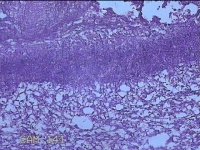

右侧窦腔内容物

性别

男

年龄

49岁

临床诊断

1.慢性鼻窦炎 2.鼻中隔偏曲 3.变应性鼻炎

一般病史

鼻塞、脓涕2月,加重伴涕中带血1周。

标本名称

大体所见

灰白暗红色不规则碎组织1.5x1.3x0.3cm一堆。

图4